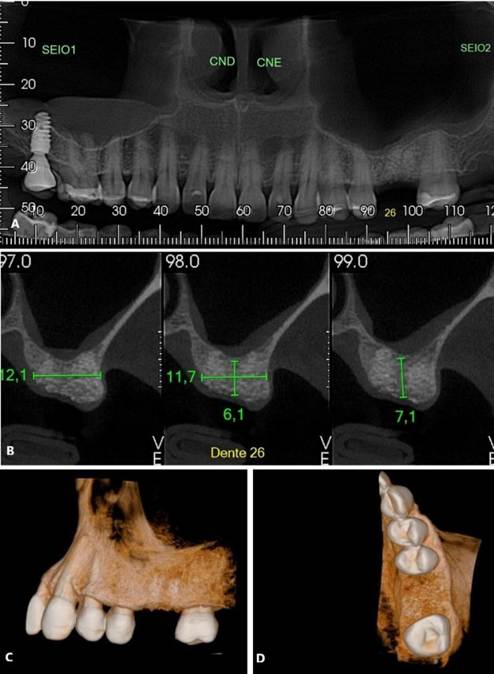

Paciente A. R. S, gênero feminino, 67 anos de idade, compareceu ao consultório particular, em 2020, com a queixa de mobilidade na região dos implantes inferiores. Na anamnese, paciente realizava acompanhamento médico devido ao quadro de diabetes mellitus, com uso de medicamentos específicos. Ao exame clínico, verificado mobilidade acentuada na regão do 36, 37, 46 e 47. Foram solicitados radiografia panorâmica (Figura 04. A) e tomografia computadorizada da área, evidenciando comprometimento periodontal avançado nas reabilitações com implantes dentários. O plano de tratamento proposto foi a remoção dos implantes e nova reabilitação da região atrófica.

Inicialmente, o procedimento cirúrgico consistiu pela remoção dos implantes dentários (Figura 04. B), realização de enxerto imediato (Bio-Oss, Geistlinch, Wolhusen – Suíça), através da técnica de reconstrução tipo tenda, e uso da membrana de colágeno (Bio-Gide, Geistlinch, Wolhusen – Suíça). O Quadro 1 apresenta as principais medidas para avaliação do posicionamento do implante. Após 6 meses, foram instalados dois implantes dentários extra curtos ARCSYS (FGM, Joinvile – SC, Brasil) 4,0 mm x 6,0 mm x 5,0 mm do lado direito e dois implantes na região esquerda 5,0 mm x 5,0 mm. As figuras 05 e 06 evidenciam aspecto radiográfico após a etapa inicial. As recomendações pós-operatórias e a prescrição medicamentosa foram realizadas, resultando em ausência de complicações após a intervenção. O acompanhamento foi feito durante 5 anos, com resultado satisfatório (Figura 7. A – E).

Figura 05. Exames de imagem da região inferior direita. A) Vista panorâmica. B) Reconstruções tridimensionais. C) Cortes transversais oblíquos.

Figura 06. Exames de imagem da região inferior esquerda. A) Vista panorâmica. B) Reconstruções tridimensionais. C) Cortes transversais oblíquos.